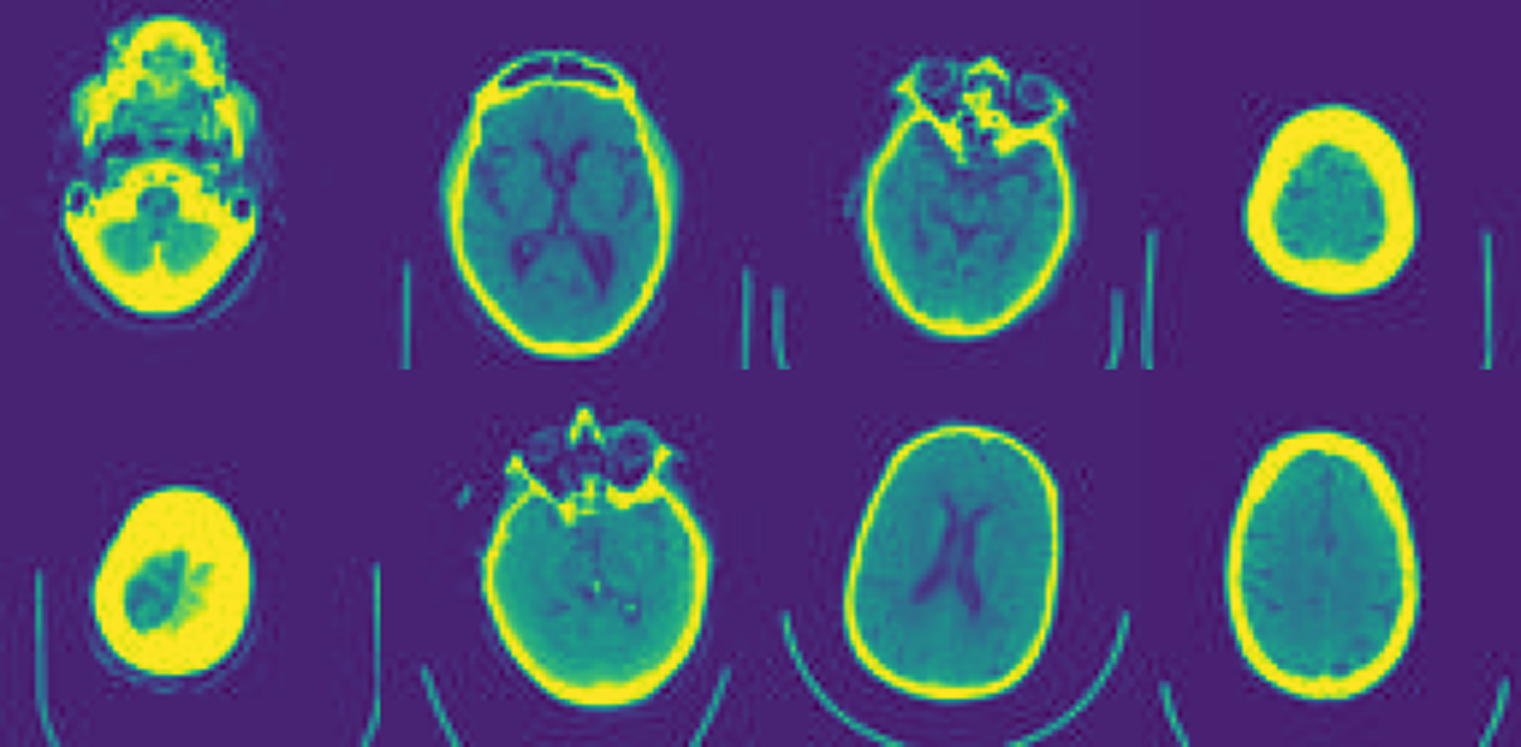

To assess the performance on anomaly segmentation, we utilized a subsample of the MedNIST dataset, where we used the 2D images of the HeadCT category to train our VQ-VAE and transformer models (Figure LABEL:fig:S1). From the original 10,000 HeadCT images, we used 8,000 images as the training set and 1,000 images for the validation set. The test set was comprised of 100 images contaminated with sprites (i.e., synthetic anomalies) obtained from the dsprites dataset Matthey et al. (2017). We selected the sprites images that overlapped a significant portion of the head, and their values were set as 0 or 1.

fig:S1